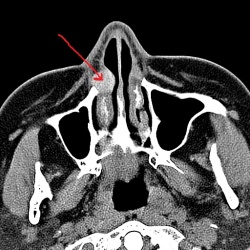

Молодая девушка направлена ЛОРом с диагнозом хр.эпитимпанит, холестеатома? справа. Терпеть не могу уши. С холестеатомой еще не сталкивался ни разу. Хотелось бы услышать ваше мнение.